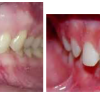

Normaalse hambumuse puhul katavad ülemised eeshambad alumisi 1/3 krooni pikkuse ulatuses ning alumiste eeshammaste lõikeserv on kontaktis ülemiste lõikehammaste suulaepoolse pinnaga.Sügavhambumuse puhul katavad aga ülemised hambad alumisi lõikehambaid rohkem kui 1/3 hambakrooni ulatuses. Raskemate vormide puhul alumised hambad ei paista ning on tekkinud traumeeriv kontakt suulae ja alumiste eeshammaste vahel. Näo välisvaatlusel on näha, et alumine näo kolmandik on lühenenud

Sügav hambumus